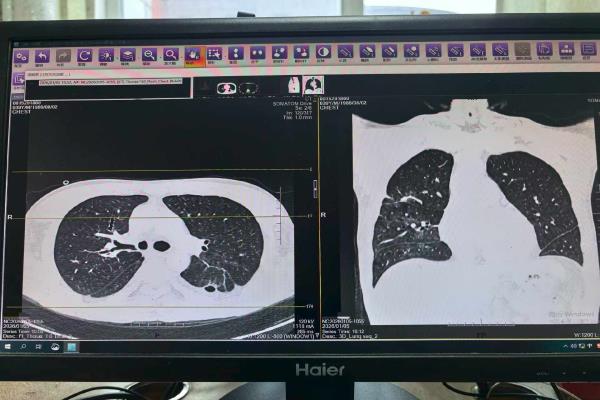

在后续CT检查中,医生发现其左肺形成了肺脓肿,并且发生了支气管胸膜瘘。“这意味着感染灶持续存在,像一个定时炸弹。”周利平说。为彻底清除病灶,经过多学科团队慎重的评估,最终为他实施了左下肺叶切除术。感染的核心被切除后,这场持久战才终于结束。术后约一周,患者即出院返渝。据随访,目前患者复查肺部CT显示,恢复良好。

男子术后CT图